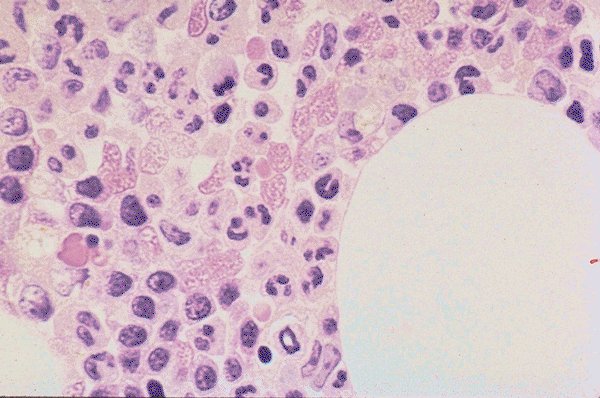

Normal marrow

This is a bone marrow biopsy under high dry

power. The stain is H&E. Normal distribution of

myeloid and erythroid cells as well as

background cells can be appreciated, as can the

degree of cellularity.